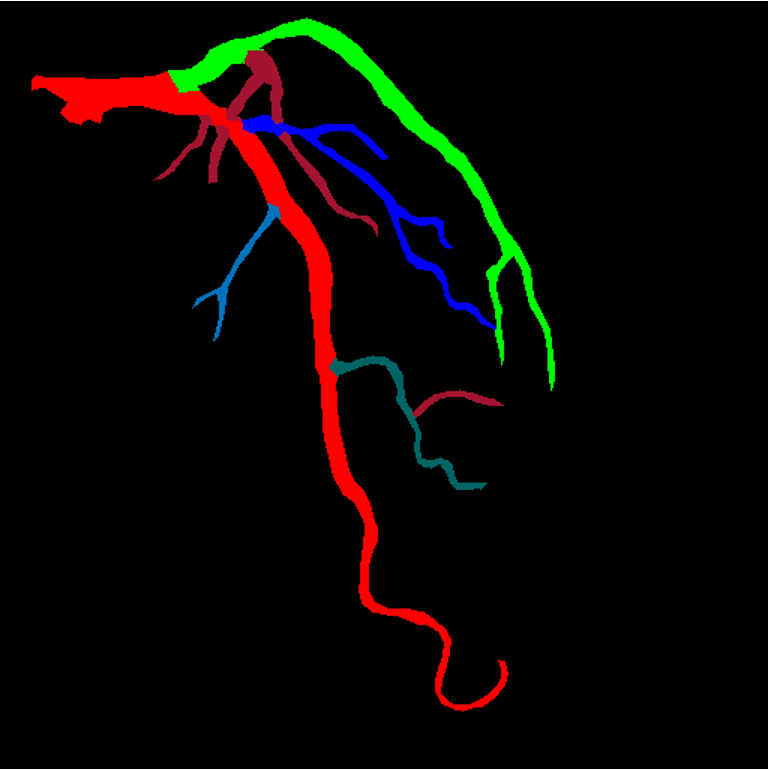

Our research interests are primarily focused on (but not limited to) Multimodal Reconstruction and Analysis of Digital Anatomy for Real-Time Clinical Interventions; in particular Segmentation, Landmark Detection, Tracking, Motion Modelling, Reconstruction, Registration, and Fusion of 2D/3D/3D+t Human Anatomical Structures (Cardiovascular, Cerebral, Biliary System, etc.) and Physiological information from Multi-Modality including X-ray, Angiography, MRI, CT, US, etc.

- Multimodal Reconstruction of Digital Heart for Cardiac Interventions in Real-Time.